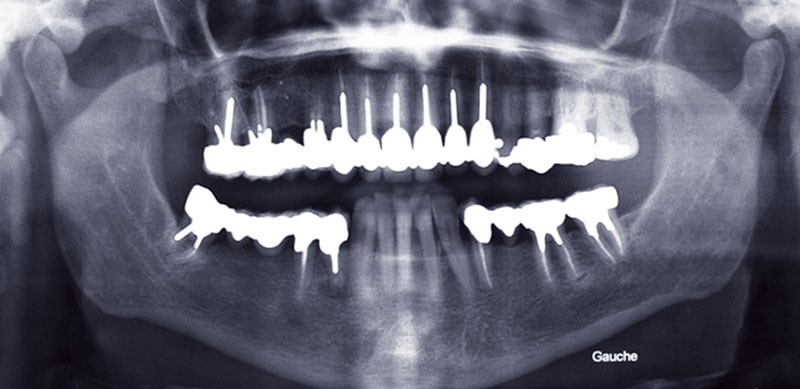

Les possibilités des techniques de collage doivent nous faire passer de concepts biomécaniques à des concepts adhésifs. Le concept suggéré par différents auteurs du « No Post, No Crown » (plus de tenon, plus de couronne) a parfois du mal à trouver une écoute attentive chez certains praticiens pour qui la notion d’acte remboursable reste un facteur majeur décisionnel dans leur thérapeutique. Ce qui peut largement se comprendre dans le système français, mais qui reste préjudiciable pour la pérennité des organes dentaires. Il faut ainsi préciser que Vailati a, dès 2008 [1], mis en avant le problème de la reconstitution d’une dent fortement délabrée dans le cas de reconstruction totale où la préservation tissulaire est le guide thérapeutique majeur. En effet, face à de fortes érosions, la motivation thérapeutique ne devrait plus être de dépulper systématiquement la dent, mettre un ancrage radiculaire métallique et réaliser une coiffe périphérique (fig. 1).